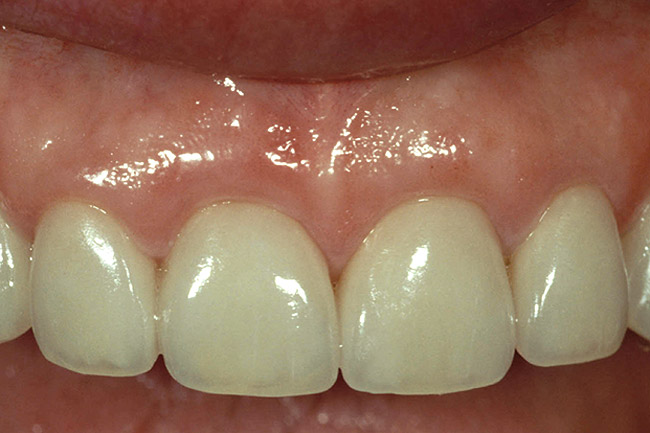

Figure 2  Note the invisibility of the marginal line in the completed veneers, even though the margin has not been carried below tissue.

Figure 2